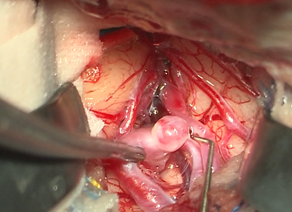

脳神経外科

a1